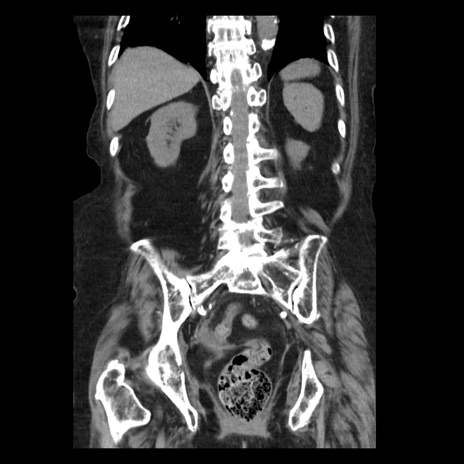

症例14(冠状断像)

【症例】 90歳代女性

【主訴】 腹痛・嘔吐

【現病歴】今朝から左側腹部痛を認めた。 経過観察していたが、嘔吐を認めたため来院。

【既往歴】 子宮癌術後

【身体所見】 意識清明、BP 127/54mmHg、P 98bpm Sp02 95%(RA)、BT 35.8°C、腹部平坦・軟腸ぜん動音聴取良好、右下腹部圧痛(+) 反跳痛なし

【データ】WBC 9800、CRP 0.46